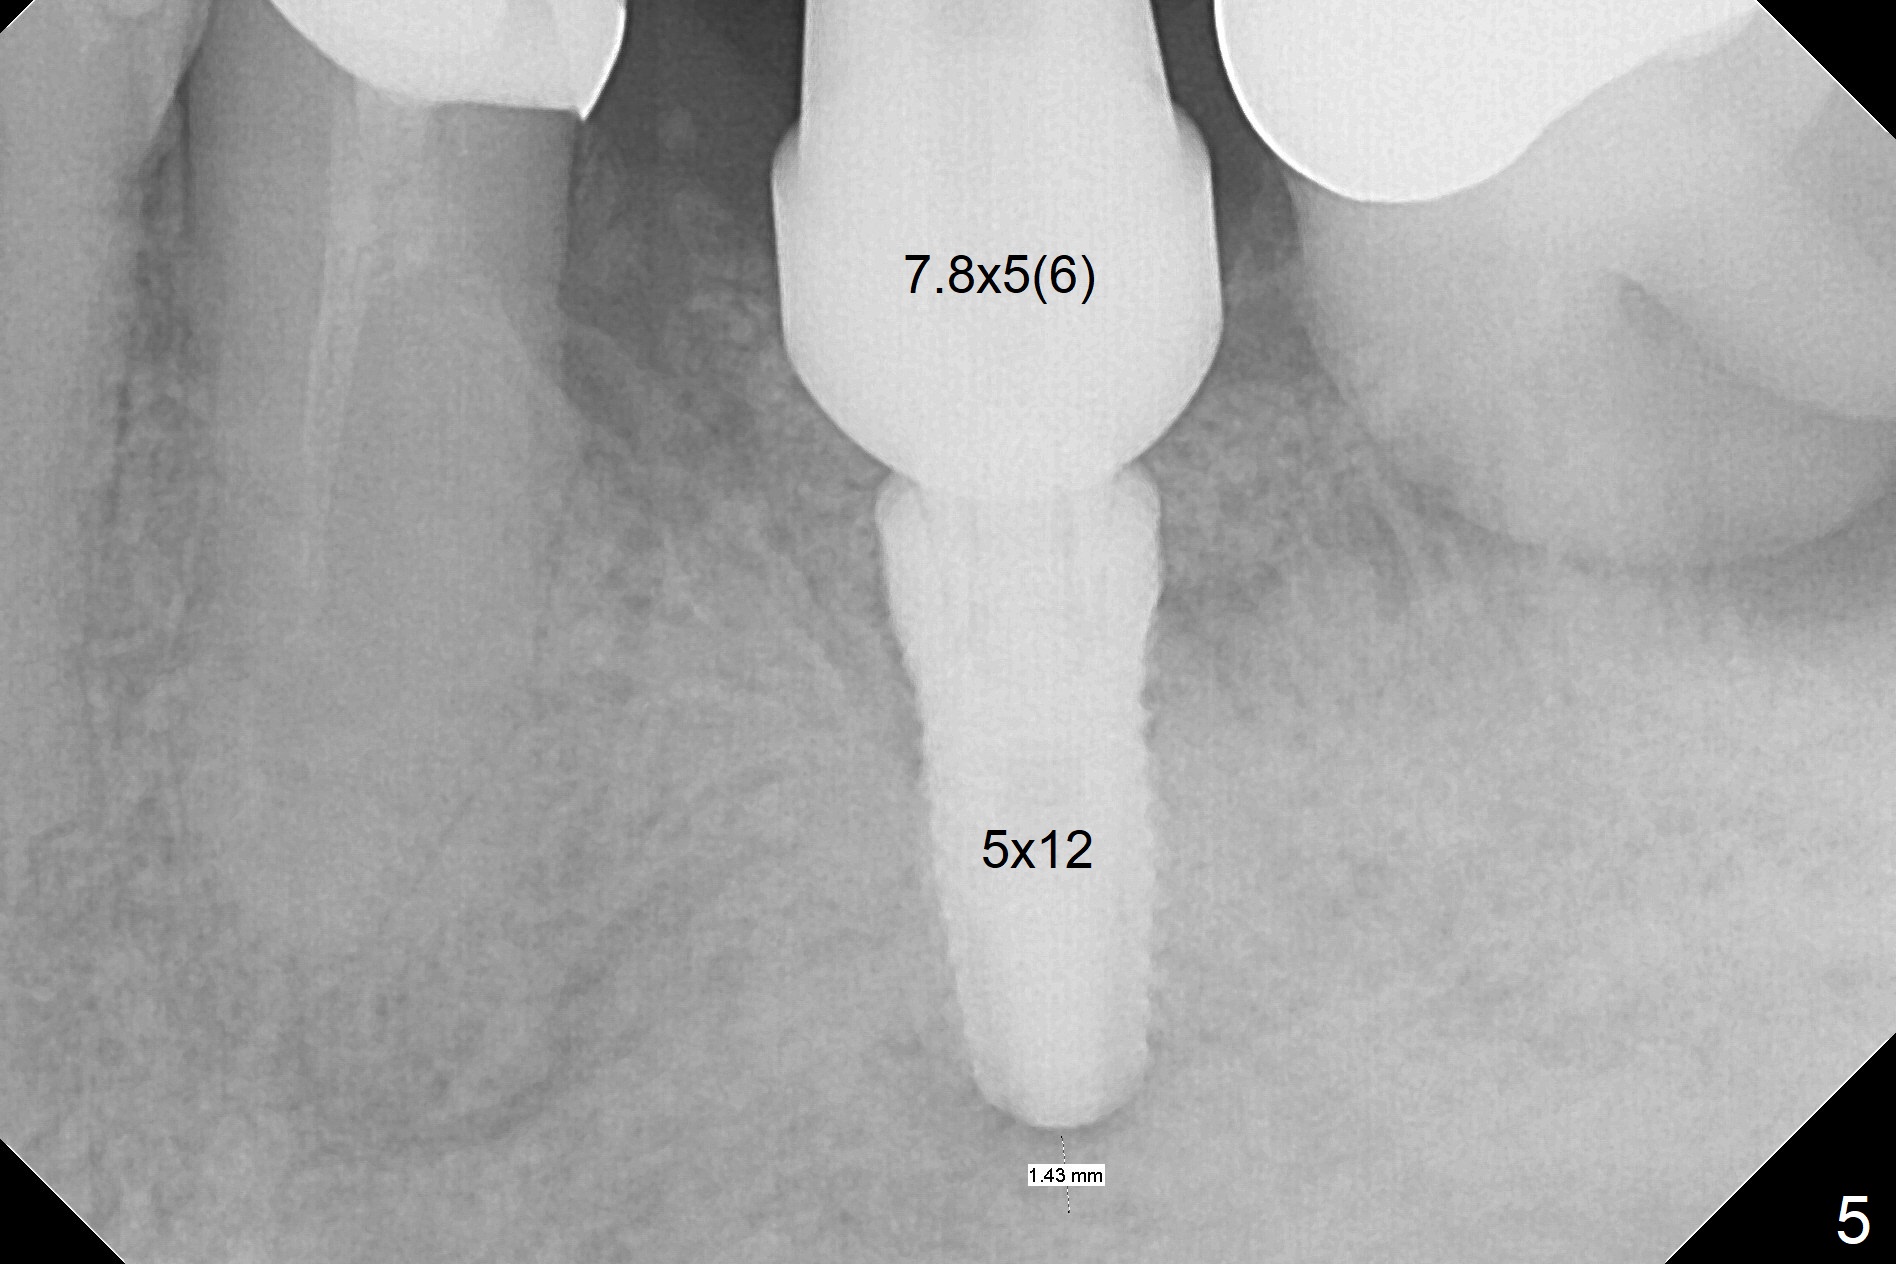

After extraction of the supraerupted tooth #19 with severe buccal gingival recession, the buccal and lingual plate are found to be lost. The sockets are fused and flat without the septum. The bone is hard and painful for the initial osteotomy with infiltration anesthesia (Fig.2). Following block anesthesia, the initial osteotomy depth extends to 8 mm (Fig.3,4). With apparent 4.9 mm clearance, the osteotomy is further extended to 10 mm. The osteotomy walls are apparently intact without severe hemorrhage after each drill. Due to the thick gingiva and severe bone loss, a 5x12 mm implant is intentionally placed 3 mm above the base of the socket bone (Fig.5,6 (yellow dashed line)). Vanilla Cortical and Cancellous allograft (Fig.6 *) is placed around the exposed implant and 7.8x5(6) mm abutment with 4 and 2 mm buccal and lingual gaps. Next collagen plug cut in strip is placed to fill the most coronal aspect of the socket (Fig.7 *). The buccal and lingual gingivae are approximated with sutures proximally. Finally periodontal dressing is applied. Since the Inferior Alveolar Canal is vague in intraop PAs (Fig.4,5), there is worry about potential nerve damage during and after osteotomy. This should be no issue if preop panoramic X-ray is reviewed with measurement (Fig.8). The bone graft appears to remain in place nearly 4 months postop (Fig.9). Two weeks later, he returns for impression. When the provisional is removed, the gingiva is unhealthy. Without the provisional and with improved oral hygiene, the gingiva is healthy one week later, but the tooth #18 is symptomatic. The latter is extracted with socket preservation (Fig.10 *). There is no apparent bone loss around the implant at #19 6.5 months post cementation (Fig.11).